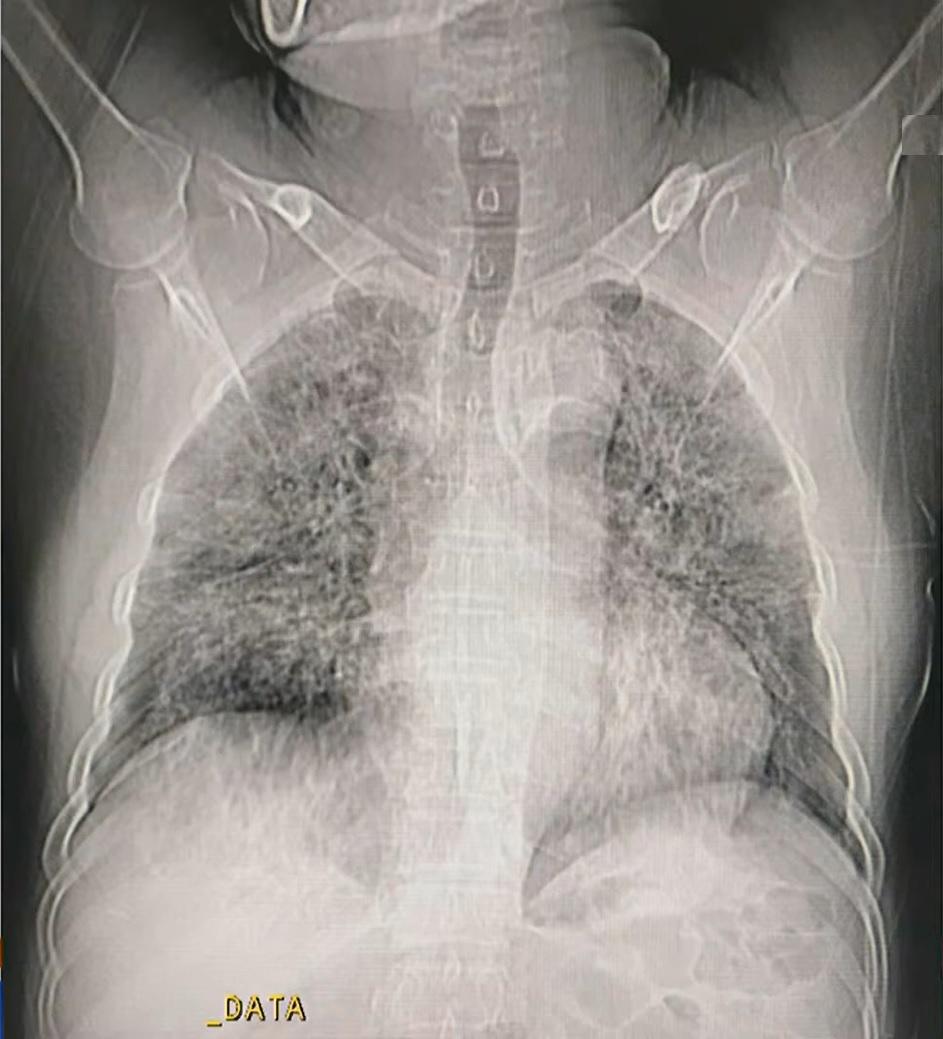

Hình ảnh chụp cắt lớp vi tính một số phân độ tổn thương phổi của người mắc Covid-19. Ảnh: Bệnh viện Đại học Y Hà Nội. |

6 phân độ (CO-RADS) nghi ngờ được xếp theo cấp độ tăng dần, trong đó, ở cấp độ 6, chắc chắn bệnh nhân nhiễm SARS-CoV-2. Cụ thể:

- CO-RADS 1: Phổi bình thường, không tổn thương.

- CO-RADS 2: Tổn thương nhưng ít và hình ảnh phổi đặc trưng cho những bệnh lý nhiễm trùng khác. Nguy cơ mắc Covid-19 thấp.

- CO-RADS3: Tổn thương có thể xảy ra ở bệnh nhân Covid-19 hoặc các bệnh phổ biến khác. Mức độ nghi ngờ trung bình.

- CO-RADS 4: Phổi có tổn thương kính mờ, dày tổ chức kẽ ở hai bên nhưng chưa đặc trưng ở bệnh nhân nhiễm SARS-CoV-2. Tuy nhiên, tỷ lệ lây nhiễm rất cao.

- CO-RADS 5: Nguy cơ rất cao. Xét nghiệm rRT-PCR lần một có thể âm tính nhưng gần như chắc chắn người này mắc Covid-19. Do đó, dựa trên cắt lớp vi tính phổi cần xét nghiệm lại cho bệnh nhân. Phổi của nhóm này có hình ảnh kính mờ, dày tổ chức kẽ, lát gạch, phân bố ở ngoại vi và đáy phổi.

- CO-RADS 6: Chắc chắn bệnh nhân mắc Covid-19, xét nghiệm rRT-PRC sẽ cho kết quả dương tính.